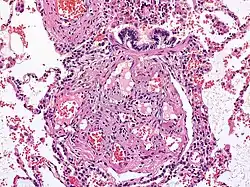

![]() Billede der viser en læsion i lungerne forårsaget af pulmonal arteriel hypertension. | |